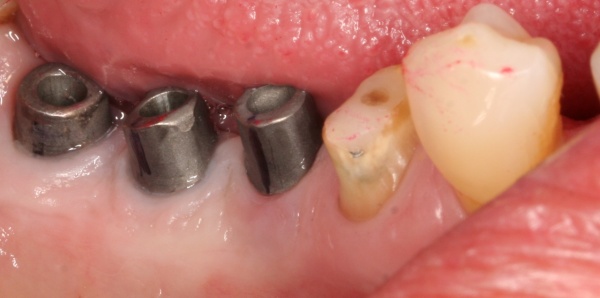

Bevor die Implantatprothetik angefertigt wird, sollten zahnärztlicherseits die periimplantären Weichgewebsverhältnisse erneut geprüft und bewertet werden. Sofern keratinisierte Gingiva periimplantär fehlt, sollte spätestens zu diesem Zeitpunkt ein weichgewebschirurgischer Eingriff (BGT, FST) erfolgen (Abb. 6).